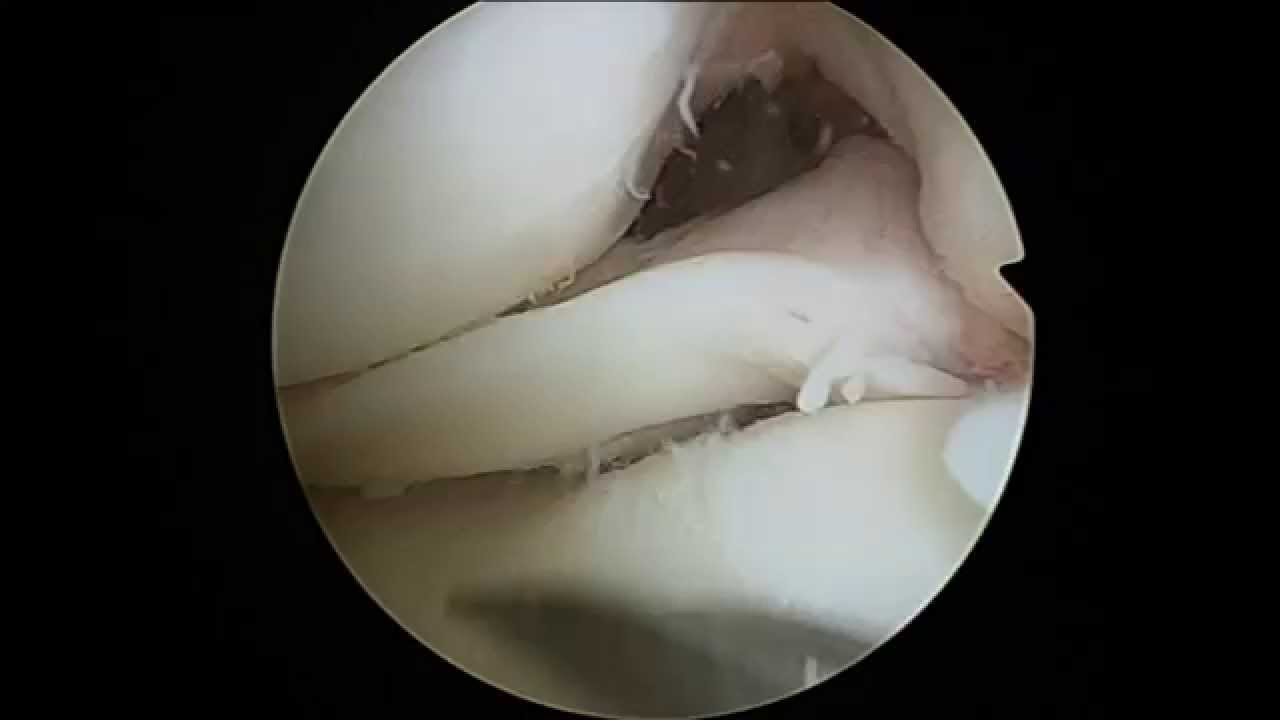

Medial Meniscus Bucket Handle Tear Repair - Knee

Medial Meniscus Bucket Handle Tear Repair - Knee from i.ytimg.com